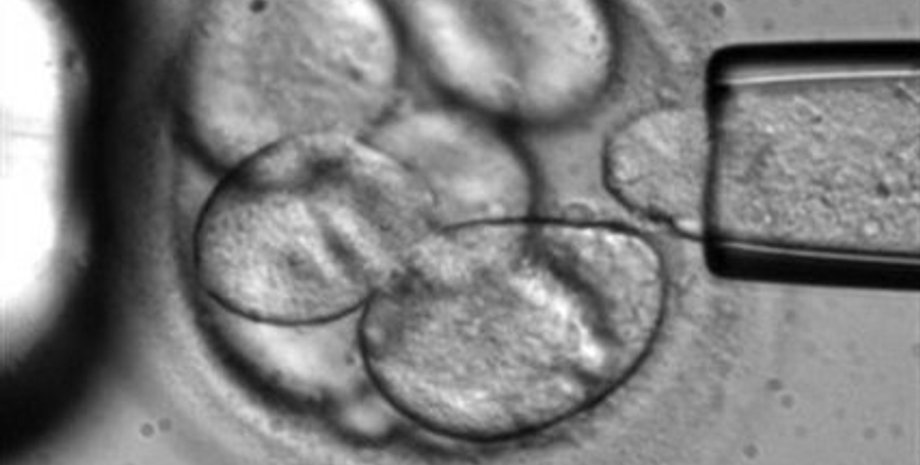

Вдохновленная успехом, Эйприл решила выставить на продажу и материнское молоко, как это делают множество американских женщин. В то же время, увеличивается количество тех, кто предлагает свои яйцеклетки для женщин, у которых есть проблемы с деторождением. Так, Shady Grove Fertility Center рассказал о росте на 13% числа доноров, достигшего в 2013 году 13 тысяч.

СМИ пишут, что многие женщины совершают это на основе альтруизма, другие - 65% - говорят, что делают это из-за экономических трудностей. "В среднем за яйцеклетку можно получить $7000 долларов", - пишет журналист.